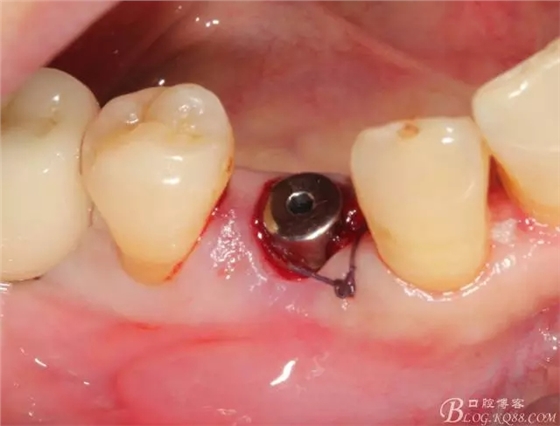

簡(jiǎn)單備洞以后植入種植體 植體和頰側(cè)空間距離大于2毫米 注意沒有植骨

這個(gè)角度更能看到植體與頰側(cè)骨壁的空間了

適當(dāng)塞入膠原塞 簡(jiǎn)單縫合